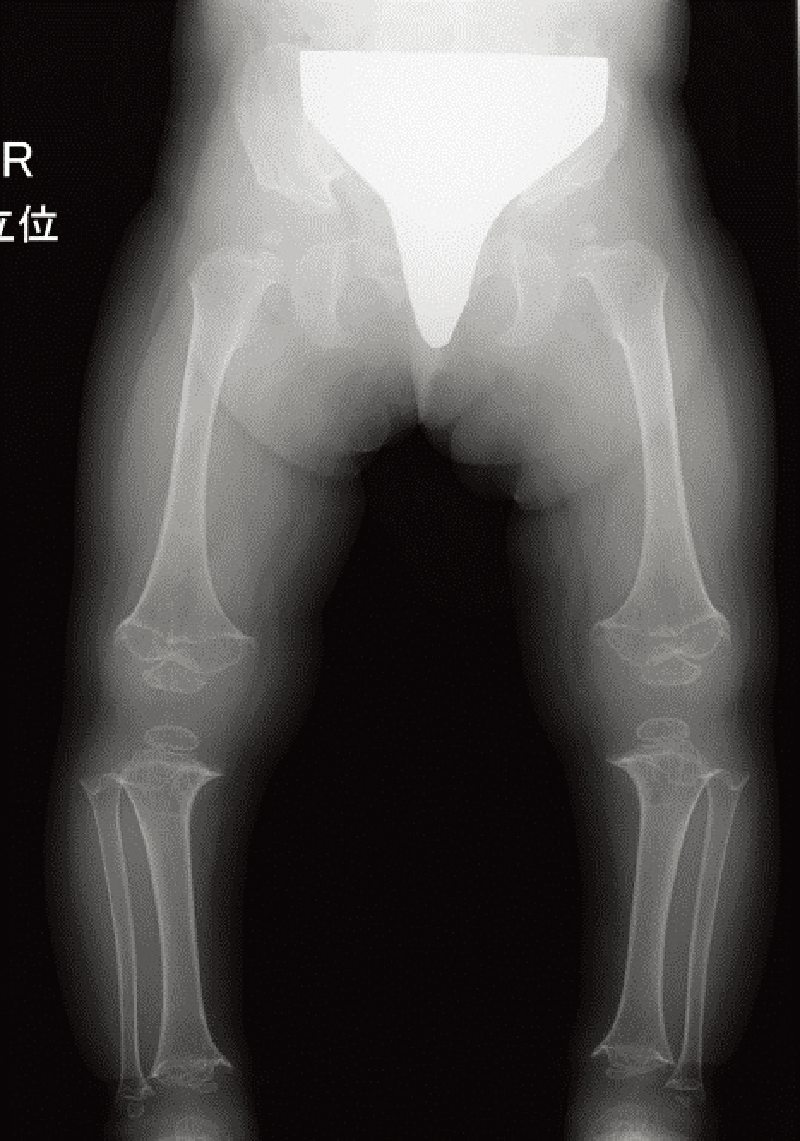

身長:低身長と著しい関節弛緩・脱臼が特徴である。

整形外科的臨床所見/特異顔貌および眼・耳などの合併症など:特異顔貌(卵型で平坦な顔、青色強膜、眼球突出など)を呈する。皮膚は柔らかく、筋緊張は低下する。進行性の脊柱変形があり(A)、下肢アライメント異常を呈することがある(B)。

特徴的な画像所見:扁平椎、腸骨低形成、軽度の骨幹端flaringが乳児期にみられる。橈骨頭亜脱臼も多くみられる。

年長児では骨端変形を認めることがある。

A. 全脊柱正面像(11歳、女):著明な脊柱側弯を認める。

B. 両下肢正面像(7歳、女):軽度の外反膝と骨端不整を認める。

ムコ多糖症と鑑別する上で重要な診断のポイント

ムコ多糖症ⅣA型モルキオ症候群と同様に関節弛緩がみられるが、程度は強い。また、顔貌が特徴的で進行性の脊柱変形が目立つ。